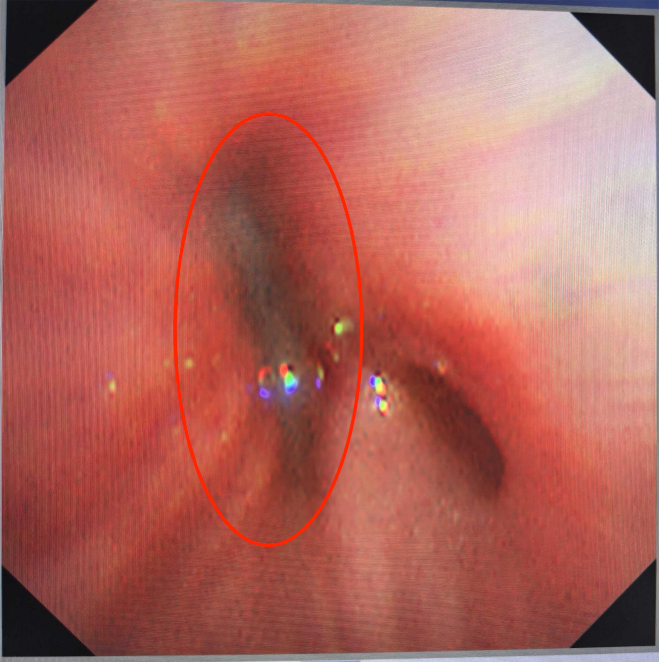

支气管塑形痰栓

钳夹+灌洗疏通气道,可立竿见影改善通气。